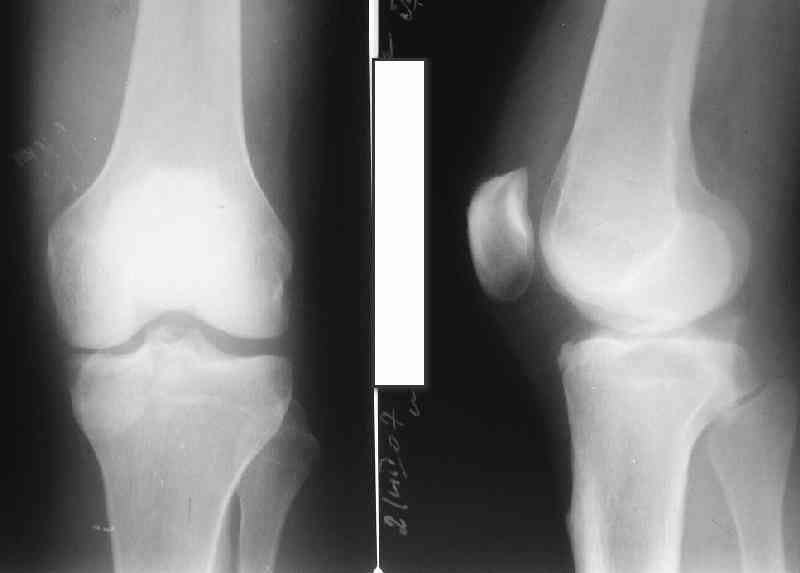

В 3 из 4 случаев мы применили винт, проведенный ретроградно по аналогии с фиксацией заднего края большеберцовой кости при переломах в

области голеностопного сустава. В прищепке рентгенограммы одного из наших пациентов до операции и спустя полгода. Остальные 3 наблюдения

описаны в статье "Изолированный отрывной перелом большеберцовой кости в месте прикрепления задней крестообразной связки // Вестник

травматологии и ортопедии им. Приорова. - 2001. - №1. – С. 38-40. Если есть интерес, могу прислать копию. Ваш случай, безуловно, отличается величиной костного фрагмента, его локализацией, характером и степенью смещения. Но думаю, принцип лечения может быть общим.

Операция из разряда травматологической "экзотики" прошла успешно. Доступ понравился:анатомичный, хорошая визуализация, удобно работать и оператору и ассистентам. Наложили пневможгут, но воспользовались им только на этапе ревизии сустава. Фрагмент развернулся на 90 град. на 2-ух "жгутах": медиально - сухожилие m.semitendinosus, латерально - задняя крестообразная связка. Мобилизовали,развернули и уложили на место без особого труда. Фиксировали отмоделированной 1/3-трубчатой пластиной. Мениск оказался неповрежден. Сустав стабилен. Обошлись без

иммобилизации, планируем начать ранние движения. Остальное на фото, дополнительно приложены корональные срезы КТ.